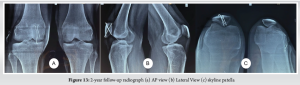

Postoperative radiographs were satisfactory (Fig. 10a and b) Immediate postoperatively, the patient was placed in a long knee brace with early initiation of passive range of motion. Knee Flexion up to 90° for 2 weeks followed by the full range of motion. Partial weight-bearing was initiated at 4 weeks followed by full weight-bearing by 6th week. The patient was regularly followed up. At the 6-month follow-up, the post-operative X-rays were satisfactory (Fig. 11a-d). However, mild patellar tilt was noted in the skyline radiograph, and the patient was advised MPFL reconstruction if symptomatic in the future. The patient clinically had no instability. The patient went on to have a full recovery and had resumed low/moderate-impact physical activity, and sports without restriction or complaints by 9 months. The knee ROM at the final follow-up was from 0° to 140° and he is completely pain-free (Fig. 12a-d). 2 year followup radiograph (Fig. 13a and b).